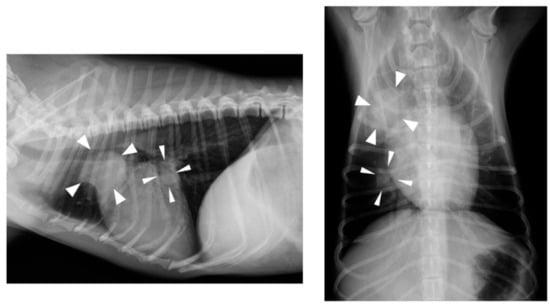

At a regular medical checkup on day 404, the dog weighed 3.1 kg and was in good general condition; however, an increase in CRP concentration (6.0 mg/dL) was observed. Thoracic radiography revealed nodular lesions in the right cranial lobe (approximately 2.0 cm in diameter) and the middle lobe of the right lung (approximately 1.0 cm in diameter) (Figure 2). Abdominal ultrasonography revealed hyperechoic nodular lesions in the right lobe of the liver (approximately 0.8 cm in diameter). Fine-needle aspiration was performed on liver nodules, but only a small number of hepatocytes were collected, and no significant findings were noted. These findings strongly suggested metastases of the ileal ASCC, but the owner opted against further examination and treatment. On day 511, the owner informed us that the dog had passed away; however, no specific details were provided.

Figure 2. Thoracic radiography findings on day 404. Nodular lesions (arrow heads) were detected in the cranial and middle lobe of the right lung.